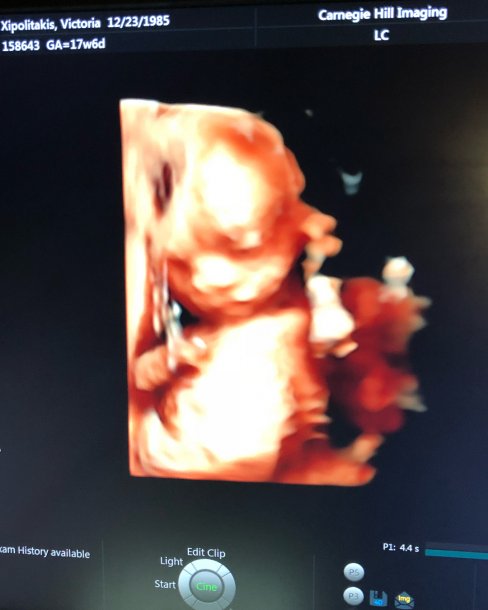

Vicky Xipolitakis transita la semana 18 de embarazo y compartió con sus seguidores la ecografía donde se nota a la perfección el rostro de Salvador Uriel. Muy contenta, la modelo mostró que, según una aplicación, el bebé mide entre 12 y 14 centímetros y pesa 150 gramos.

“Y con ustedes, les presento al milagro de cuatro meses: @salvadorurielok Hoy cumple 18 semanas, ya mide como un pimiento y me regalo estas imágenes; es la primera vez que le conozco la carita y no quería dejar de compartirlo con ustedes” #SeMeExplotaElCorazónDeFelicidad ¿Lo ven parecido a mí?”, escribió Vicky en su cuenta de Instagram.